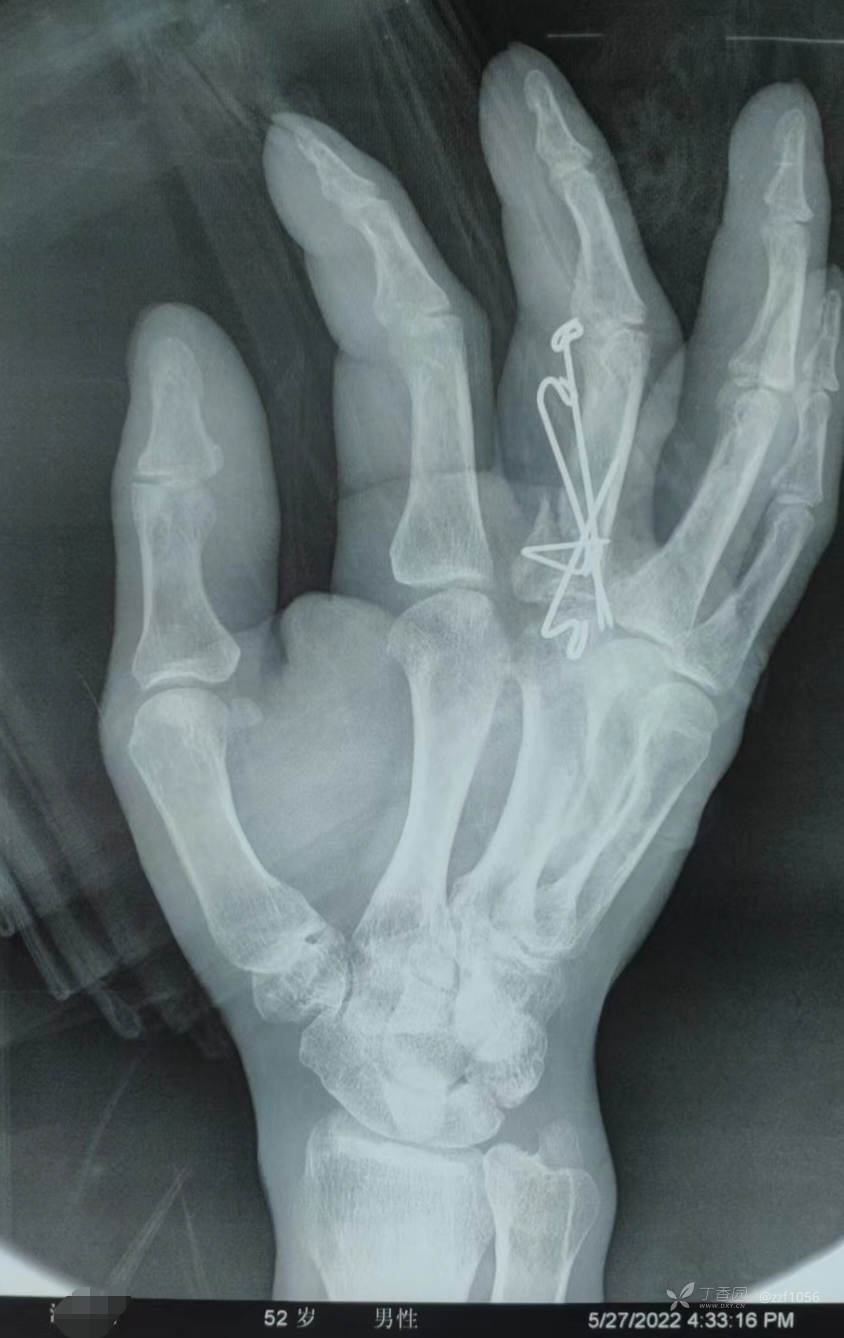

打开部分关节囊见骨折涉及软骨面,基本平整,原痕迹小心凿开,近折端爆裂了,还好软骨完整

复位费了点事,4枚针植入后相对稳固

旋转畸形矫正